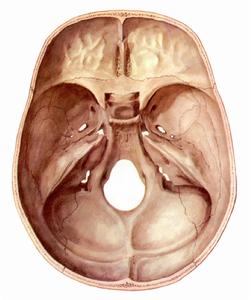

病程緩慢,大小不等的囊狀物突入顱內引起相應症狀。早期腫瘤體積小時病人可無症狀,腫瘤達到一定體積時引起腦神經麻痹和頭痛。如發生在蝶骨和鞍區附近 發生於顱中窩底的巨細胞瘤可能出現相應部位的臨床各表現。腫瘤可能表現出很強的侵犯性 甚至造成病人死亡。

蝶骨和鞍區附近的腫瘤可引起視力障礙、視野缺損以及動眼神經、展神經和三叉神經受損症狀。發生於顱中窩底的巨細胞瘤可引起反覆感染及聽力下降。

顱內巨細胞瘤應與好發部為常見的其他腫瘤鑑別,如脊索瘤、大的垂體瘤、鼻咽癌以及轉移癌等。由於顱骨巨細胞瘤惡性程度相對較高 所以在組織病理上應該與發生部位相同的含巨細胞的腫物相鑑別,包括巨細胞修復性肉芽腫、甲狀旁腺功能亢進、成軟骨細胞瘤、骨纖維結構不良和動脈瘤樣骨囊腫巨細胞修復性肉芽腫可侵犯面頰、顎部以及顎外區域的骨質,巨細胞修復性肉芽腫有不規則片狀分布的巨細胞,成纖維膠原基質上有骨質化生。巨細胞修復性肉芽腫的一致特徵是圍繞巨細胞的細胞呈細長形。甲狀旁腺功能亢進與巨細胞修復性肉芽腫的組織學特徵相同 必須通過實驗室檢查來鑑別二者。成軟骨細胞瘤比巨細胞修復性肉芽腫更少見,它的特點是局部軟骨分化增生,形成結節樣或帶狀的深染上皮樣細胞巨細胞和血鐵質色素顆粒分散分布動脈瘤樣骨囊腫和骨纖維結構不良可以通過梭形細胞增生的成纖維特性,以及骨質生成的結構,與骨巨細胞瘤區分偶爾骨巨細胞瘤與轉移癌病理區分困難,需要尋找原發灶,明確診斷。巨細胞修復性肉芽腫通常可以通過單純手術治療控制,不需要放射治療。而放療是顱骨巨細胞瘤完整治療的一部分,單獨手術治療不能控制病情的發展。所以鑑別骨巨細胞瘤和巨細胞修復性肉芽腫有重要意義。